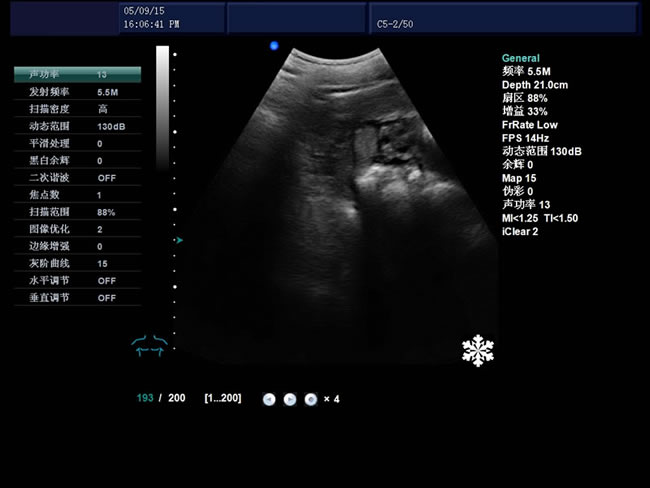

S9 彩色多普勒獸用超聲診斷儀

• S9彩色多普勒獸用超聲診斷儀是徐州市大為電子設備有限公司推出的一款全新的彩色超聲診斷儀器。

• 臨床應用